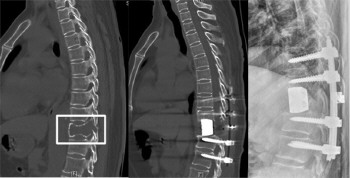

我们都知道,人体脊柱结构大概可以比作一串冰糖葫芦,山楂是脊椎骨,竹签是脊髓。如果脊椎骨病变需要换掉而又不损伤极度柔弱的脊髓,这样的手术难度可想而知。近日,滨医附院就做了这样一例手术,并用3D打印脊椎骨替换掉病变脊椎骨,重建人体脊柱。

患者因感背痛并逐渐加重入住滨医附院脊柱外科,经过检查,高度怀疑为脊柱原发肿瘤,且肿瘤椎体及附件骨质已被严重侵蚀,随时有发生病理性骨折及脊髓压迫瘫痪可能。脊柱外科团队经反复术前讨论,认为可为病人实行一期全脊椎整块切除进行治疗。全脊椎整块切除术是近年来脊柱肿瘤最前沿的手术方式,该手术首先从后方经椎弓根将病变节段的后部结构整块切除,再将椎体一并整块切除,最后重建脊柱前中柱。该术式具有肿瘤切除彻底的优点,能够将肿瘤细胞对其它正常组织的污染风险降到最低。但脊柱肿瘤的治疗历来是脊柱外科的难点,全脊椎整块切除手术尤其风险大,稍有不慎挤压到“娇嫩”的脊髓,就会导致患者瘫痪,而且容易损伤胸腹部大血管和椎内静脉丛等导致大出血,目前国内只有少数三甲医院有成功的经验。

经过周密的术前准备,在麻醉科(手术室)的配合下,脊柱外科耿晓鹏医疗团队,历时7小时,顺利地将肿瘤椎体作为一个整体完整地切除下来,完成了脊柱肿瘤一期全脊椎整块切除并3D打印人工椎体重建术。整个手术顺利,共输血1500ml,术后生命体征平稳,下肢活动良好,顺利度过围手术期,目前已康复出院。